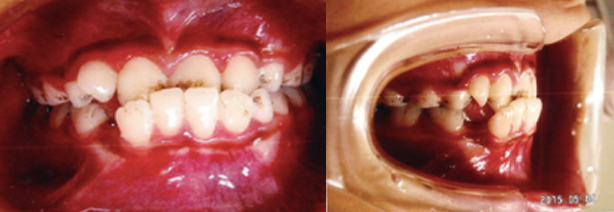

受け口(反対咬合)

通常上の歯と下の歯を噛み合わせた場合、上の歯が下の歯の前にきますが、反対に下の歯が上の歯の前に来ている状態を、受け口(反対咬合)と言います。

-

治療前

-

治療後